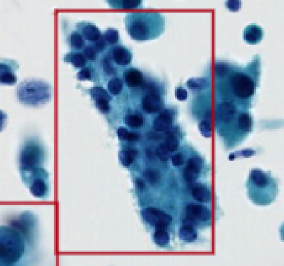

Identify Pattern

1. Wrinkles and foids

2. Slide impurities

3. Cracks

4. Voids